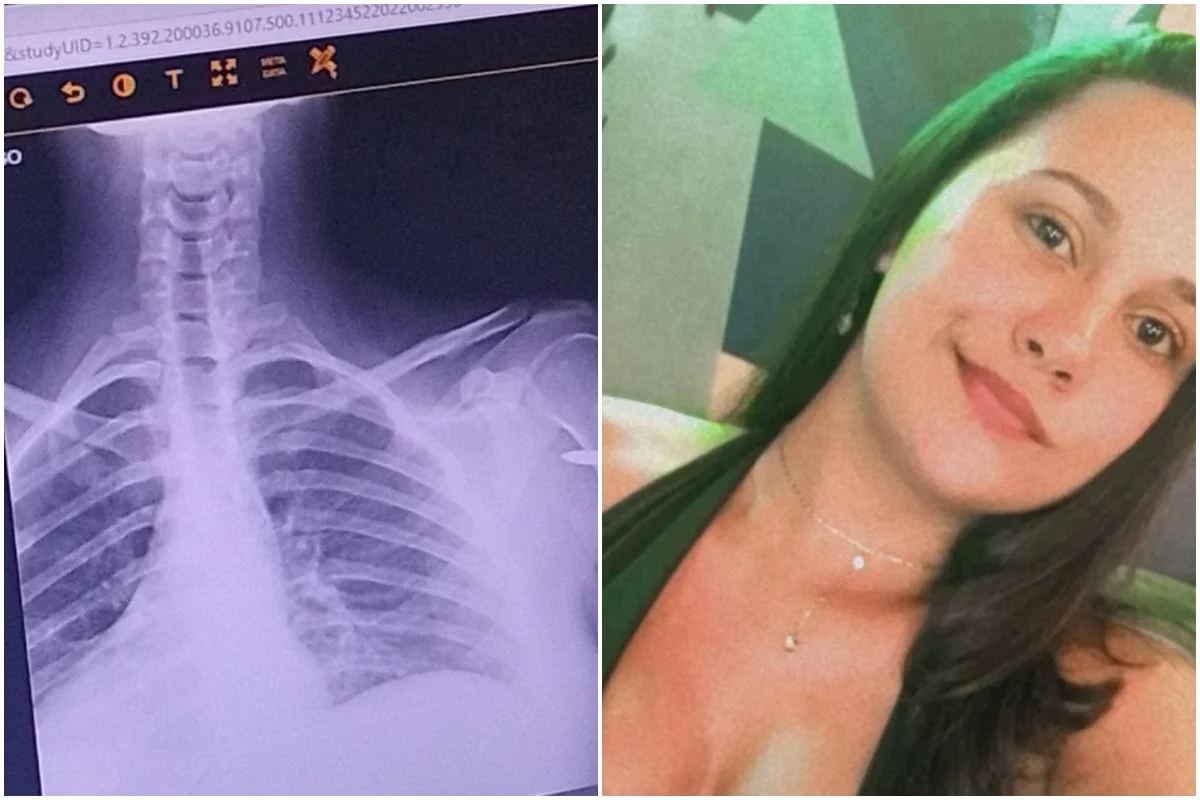

Uma estudante chamada Renata de Assis, de 22 anos, foi baleada em um pagode na região de Rocha Miranda, Zona Norte do Rio de Janeiro. A jovem só percebeu o que havia acontecido quatro horas depois. Na ocasião em questão, ela comemorava o aniversário de uma amiga, e só foi perceber que havia uma bala alojada em seu braço quando foi para a emergência.

Renata conta que quando chegou em casa, na madrugada de domingo, falou do machucado para sua mãe, que logo convenceu a jovem a procurar um médico e ver do que se tratava. Ao chegar na unidade de saúde na UPA da Penha, Zona Norte do Rio de Janeiro.

“O que eu senti foi medo, desespero, achar que eu ia morrer e nunca mais ia sair de lá. Eu pensei ‘pronto, quando vê a plaquinha de emergência do hospital, você não sai mais. Acabou pra mim’. Agora, eu estou bem. Estou só com uma bala no meu braço, mas estou bem”